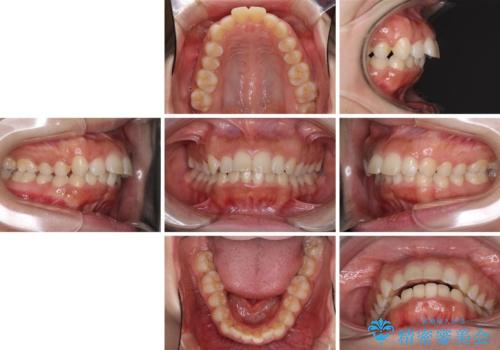

上下顎ともに前突しており、特に上顎は著しい突出感でした。

また、下顎歯列には左右差があり、非対称な抜歯が必要と判断されたため、治療は困難なものとなりました。

それでも根気強く通院してくださり、横からの顔貌の印象が大きく改善され、スムーズに口が閉じられるようになりました。

- 口元の突出感と口の閉じにくさを気にして来院された患者様です。

上下左右の小臼歯4本を抜歯し、ワイヤー装置にて口元を引っ込めるよう矯正治療を行うこととしました。